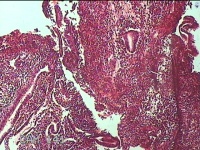

宫腔内容物

性别

女

年龄

36岁

临床诊断

异常子宫出血 附件囊肿改变

一般病史

阴道不规则流血17天。

标本名称

大体所见

灰白暗红色不规则碎组织1.8x1.3x0.3cm一堆。

图1

经期内膜+增殖期内膜。